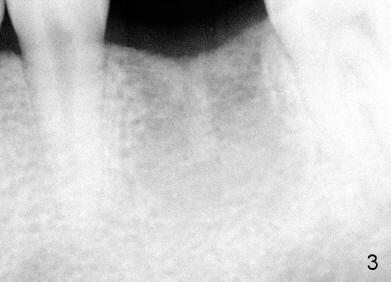

A 22-year-old man requested extraction of the tooth #19 (Fig.1).  X-ray was taken 3 and 8 months post extraction, respectively (Fig.2,3).  A 6x17 mm Tatum tapered implant was placed (Fig.4,5). A 5 mm (in diameter) 0 degree unipost (5 mm in height) was prepared 7 months after implant placement. Due to limited space, time was spent for extraoral and intraoral reduction of the abutment.